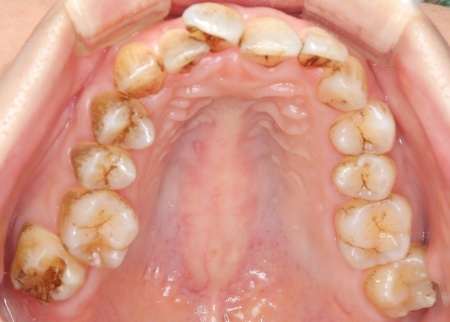

30代女性 デコボコした歯並びをワイヤー矯正とセラミック治療で改善した症例

拝見したところ、歯が全体的にずれたりねじれたりして生えており、歯並びがデコボコしていました。 また、数本の歯にはプラスチックの詰め物が装着されていましたが、経年的な劣化により歯との間に段差が生じています。これも噛み合わせのバランスを崩す原因のひとつになっていると考えられました。 歯並びや噛み合わせの乱れをこのまま放置すると、歯磨きがしにくくなり虫歯や歯周病のリスクが高まるほか、特定の歯に強い力がかかり続けることで将来的に歯の寿命に影響を及ぼすおそれもあります。

診断結果を踏まえ、まずはワイヤー矯正で歯並びと噛み合わせを整え、その後に形が変化している歯や劣化した詰め物を白いセラミック素材で作り直す治療計画を提案し、同意いただきました。 この治療方法であれば、歯を動かして噛み合わせの位置関係をしっかりと整えたうえでセラミックによる修復治療を行えます。また金属を使用しない白い素材を用いるため、見た目の違和感を抑えられます。 また、下の左右に半分埋まっている親知らず(第3大臼歯)があるため、矯正治療の際に抜歯する必要があることをお伝えし、ご了承いただきました。 まず親知らず2本を抜歯し、ワイヤー矯正治療から開始します。

治療前